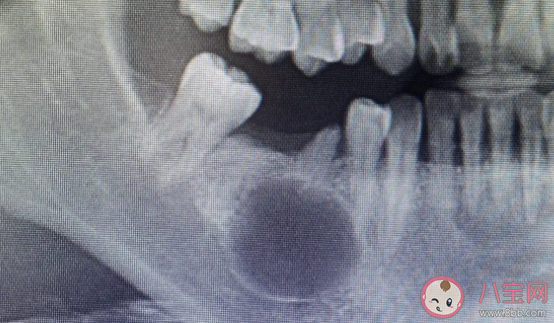

牙瘤是牙源性肿瘤中的一种,生长于颌骨内,是以牙体组织杂乱排列成团或形成数量不等畸形牙为特征的牙发育畸形,并非真性肿瘤。

“牙瘤”通常生长在颌骨中的牙骨附近。虽然“牙瘤”本身不会转移,但如果不及时进行治疗,它可能对口腔健康造成影响。数据显示,“牙瘤”疾病的患病率在过去几年里呈上升趋势。相关专家认为,这一增长趋势与现代生活方式的改变有关,包括营养不良饮食、不正确的口腔卫生习惯以及长时间的吸烟和饮酒。

总之,牙瘤病因较复杂,多种因素均可能与牙瘤的发生相关,如乳牙的慢性炎症和感染遗传因素、成牙本质细胞过度反应等。牙瘤患者常有缺牙现象,牙瘤可引起恒牙迟萌、疼痛、颌骨膨隆、邻牙移位、松动,病变范围较大,可导致骨缺损甚至引起骨折。

如果发现长了牙瘤,需尽早手术切除,否则随着瘤体增大。发生在下颌骨的牙瘤会压迫下颌骨内的下牙槽神经,从而出现下唇麻木等症状;发生在上颌骨的牙瘤,可能会压迫眶下神经,出现眶下区皮肤麻木症状,或者继发感染,出现局部炎症和疼痛;如果反复继发感染,会严重影响日常生活。

牙瘤手术的实施难度与瘤体生长的位置有关,如果牙瘤处于颌骨内,需要在右下颌后牙区开展手术,术野范围局限以及埋伏恒牙临近下牙槽神经区域,会增加手术难度和术中风险。